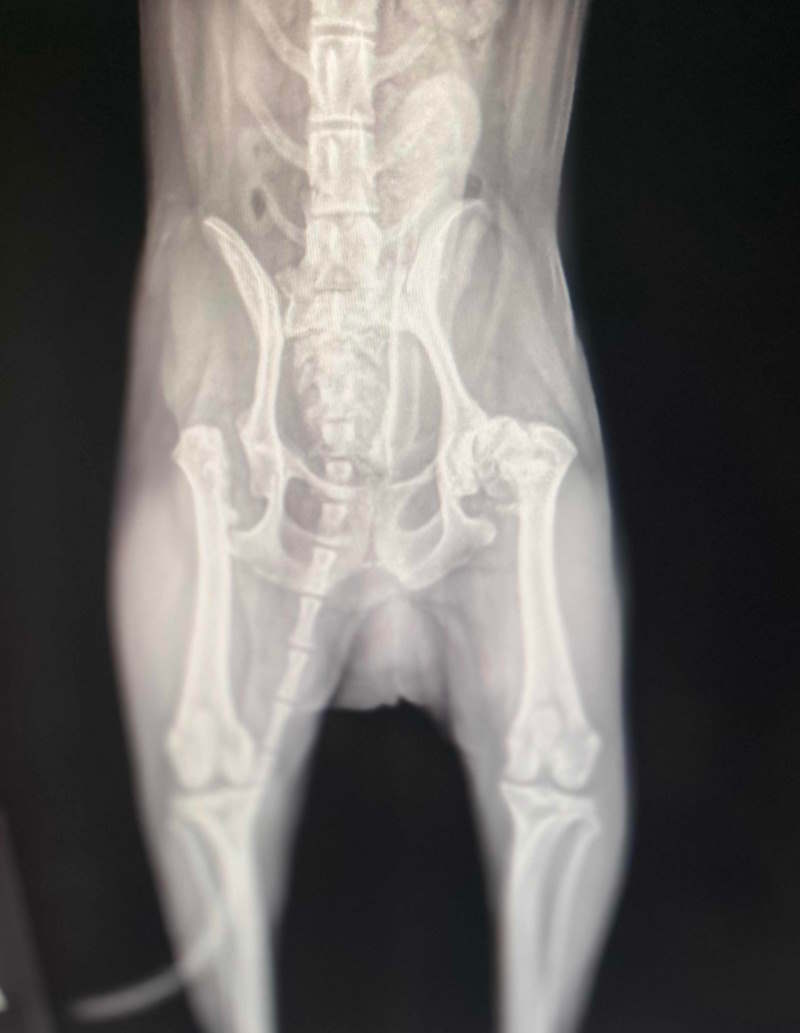

I promised I would address hip dysplasia in tiny dogs. Please meet my tiny dog, Ketchikan, a purebred 4 pound Shih Tzu.

His hip x-rays were fine for the first 3 years of life and he was used in a breeding program. By the time he was 5, he was having pain issues even though he was on a high quality diet and a moderate amount of exercise.

He was never a jumper and we had to purchase dog stairs and a ramp for him to use because he loved sleeping in my bed.

He was eventually treated with a femoral head ostectomy which helped for a while, but by the time he reached 8 years old, he experienced pain again, this time on the other side of his body.

Again, he was diagnosed and underwent another femoral head ostectomy. At nine, he is doing fine even though he has had bilateraly femoral head ostectomies. Size doesn't discriminate against hip dysplasia.

A definitive diagnosis can only be achieved through an X-ray often conducted under sedation or anesthesia for better image quality.

The X-ray might show severe changes but not necessarily reflect the dog’s pain level since many dogs with severe dysplastic hips can still run, jump, and appear unperturbed by their condition.

Unfortunately, an X-ray cannot predict the level of pain a dog might be suffering. According OFA, there are many dogs suffering with severe dysplastic hips that run, jump and play as if nothing is wrong.

Then, there are dogs will little obvious changes on the X-ray that are lame, limping and in obvious pain.